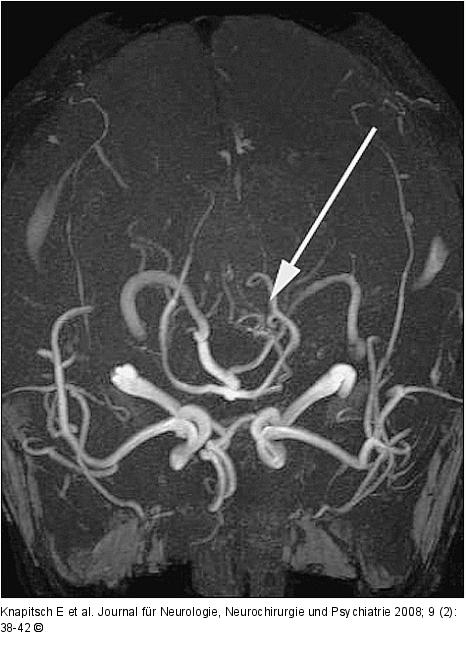

Abbildung 2: FPS Initiale Magnetresonanzangiographie (MRA): Hinweis auf eine arteriovenöse Malformation (AVM) der Arteria cerebelli superior links. |

Initiale Magnetresonanzangiographie (MRA): Hinweis auf eine arteriovenöse Malformation (AVM) der Arteria cerebelli superior links. |